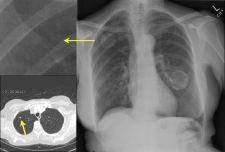

IQQA-Chest Enterprise offers a new generation enterprise CAD (computer-aided detection) solution for chest DR/CR. It provides a comprehensive set of real-time interactive tools to support physicians in the identification, confirmation and quantification of lung nodules.

One recent prospective study (van Beek et. al. Academic Radiology 2008; 15:571–575) showed a sensitivity increase of nodule detection from 63.8 percent without IQQA-Chest to 92.7 percent with IQQA-Chest assistance.